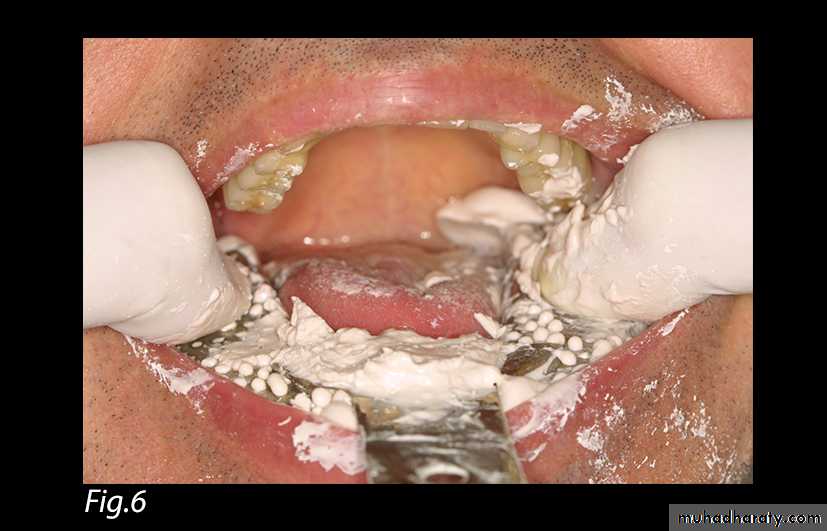

5. While the metallic tray is being loaded with an alginate impression material (Jeltrate, Dentsply Caulk, Milford, DE), this same material is used to fill the space between the soft tissue impression and the remaining teeth.6. The loaded metallic tray is inserted into position over the teeth and the acrylic tray. The index fingers are positioned on the tray facing the edentulous areas, and a positive pressure is exerted upon the metallic tray until the alginate impression material sets (Fig. 6). The completed impression is removed (Fig. 7). This maneuver permits to relate the edentulous ridge to the residual teeth in a functional state.

Fig. 6: Loaded metallic tray with a positive pressure.